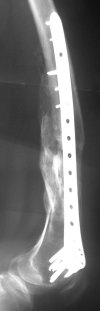

Attached are few examples from our Hospital:

A. Difficult reductions, even in retrograde nailing (my preference, easier control of "small" distal fragment) and it is much, much harder to do it anterograde (Alex, do you have one good case in your collection of anterograde nailing in very distal fractures - as you have suggested that I

should have done it in my previously posted case?

Malpositioning is much too common (recurvatum, varus - valgus).

B. Fixation loosening: distal cutting of the nail, non-unions do happen (cases attached).

Locking Plating has more distal screws than any nail, fixed angles and provides much better fixation, especially in osteoporotic bone.